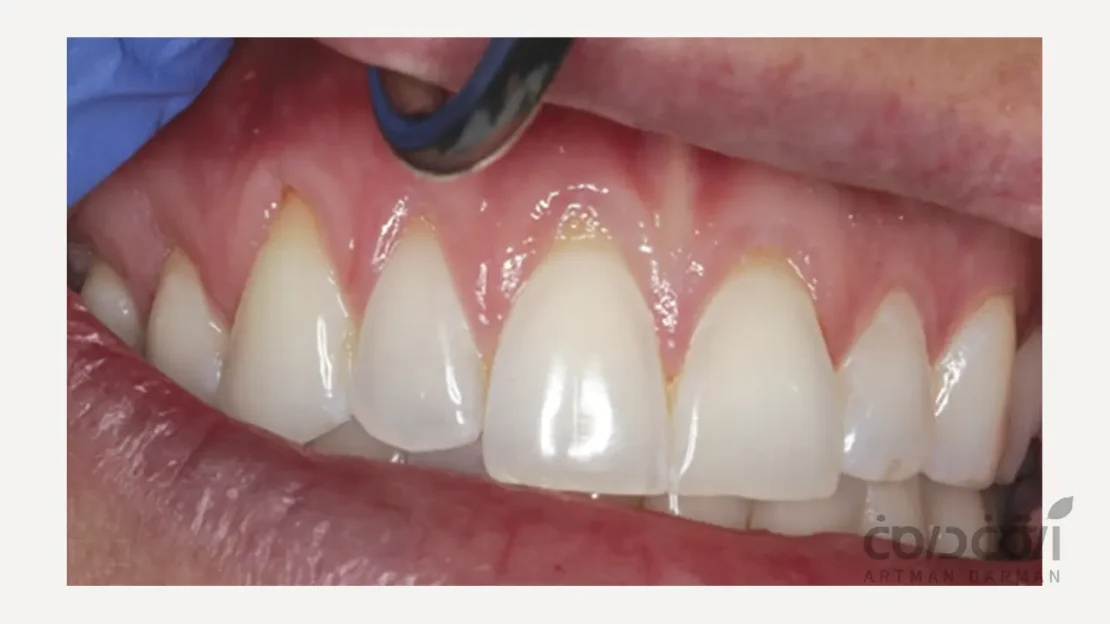

چرا باید نخ دندان استفاده کنیم؟ (+ راهنمای نحوه استفاده از نخ دندان)

برای حفظ سلامت لبخند، توجه به بهداشت دهان و دندان ضروری است.با وجود اینکه مسواک زدن یکی از روش‌های متداول حفظ بهداشت دهان و دندان است، ...